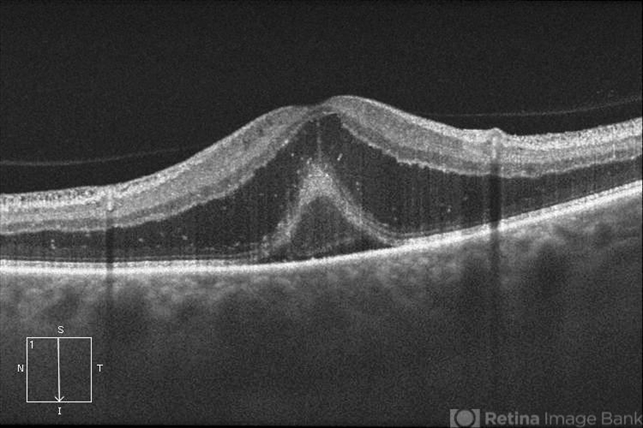

- optic neuritis, neuroretinitis

- Jason S. Calhoun, Department of Ophthalmology, Mayo Clinic Jacksonville, Florida

Optical coherence tomography system

ZEISS OCT CIRRUS - Description

- Patient with some loss of vision in his left eye and was seen for an evaluation. Patient also complained of pain in left eye with eye movement. VA was 20/400 in the left eye. Fundus photo and HD-OCT imaging show optic nerve swelling and fluid underneath the retina. A neuro-ophthalmologist will be consulted for further evaluation.